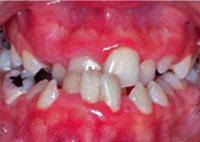

Caso 1: Paciente D. CH.

Edad cronológica: 9 años 10 meses.

Edad ósea según atlas de Greulich y Pyle:............ 8 años 10 meses

Maloclusión: Clase II División 1.

Tratamiento: Ortopédico funcional y con aparatología ortodóncica fija.

ESTUDIO DE EDAD ÓSEA:

La epífisis del cúbito, está un poco aplanada para formar la placa ósea, la forma exacta varía en los diferentes niños. El borde distal es cóncavo y presenta un proceso estiloideo diferente.

La superficie articular metacarpiana del hueso grande está comenzando a formarse. La porción del hueso ganchoso que articulará con la base del 5to. hueso metacarpiano está alargándose. Las superficies de los huesos escafoides y semilunar en relación con el radio comienza a definirse.

El margen distal del hueso escafoides, se encuentra un poco aplanado y su porción media se presenta alargada hacia el hueso grande. Se puede observar el comienzo de formación del hueso pisiforme.

Las superficies proximales de las epífisis del 2do, 3ero., 4to. y 5to. huesos metacarpianos están bastante cerca de las diáfisis y las epífisis de las falanges medias y proximales del 2do., 3ero. y 4to. dedo están tan amplias como las diáfisis.